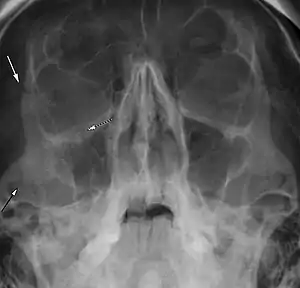

| Right zygomaticomaxillary complex fracture with disruption of the lateral orbital wall, orbital floor, zygomatic arch and maxillary sinus. | |

The zygomaticomaxillary complex fracture, also known as a quadripod fracture, quadramalar fracture, and formerly referred to as a tripod fracture or trimalar fracture, has four components, three of which are directly related to connections between the zygoma and the face, and the fourth being the orbital floor. Its specific locations are the lateral orbital wall (at its superior junction with the zygomaticofrontal suture or its inferior junction with the zygomaticosphenoid suture at the sphenoid greater wing, separation of the maxilla and zygoma at the anterior maxilla (near the zygomaticomaxillary suture), the zygomatic arch, and the orbital floor near the infraorbital canal.